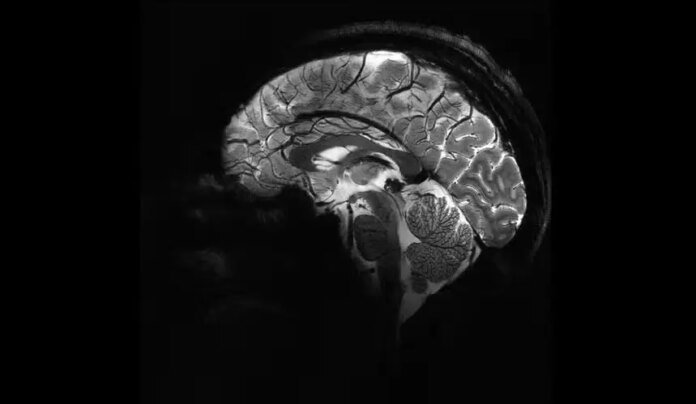

Imagem do Iseult Magneton 11.7 T MRI mostra cérebro humano. — Foto: Divulgação / Comissão de Energia Atômica da França (CEA)

A autópsia revelou uma hemorragia subaracnóidea — um tipo de sangramento no espaço ao redor do cérebro. A análise identificou um aneurisma sacular rompido, com 11 milímetros de diâmetro, uma forma comum desse tipo de condição, também chamada de “aneurisma em baga”.

“Quando os aneurismas se rompem, eles liberam sangue que pode matar células cerebrais próximas e aumentar a pressão dentro do crânio. À medida que a pressão aumenta, o fluxo de oxigênio e sangue para o cérebro pode ser interrompido, o que pode levar à inconsciência e à morte”, explicaram os médicos no relatório, segundo a LiveScience.